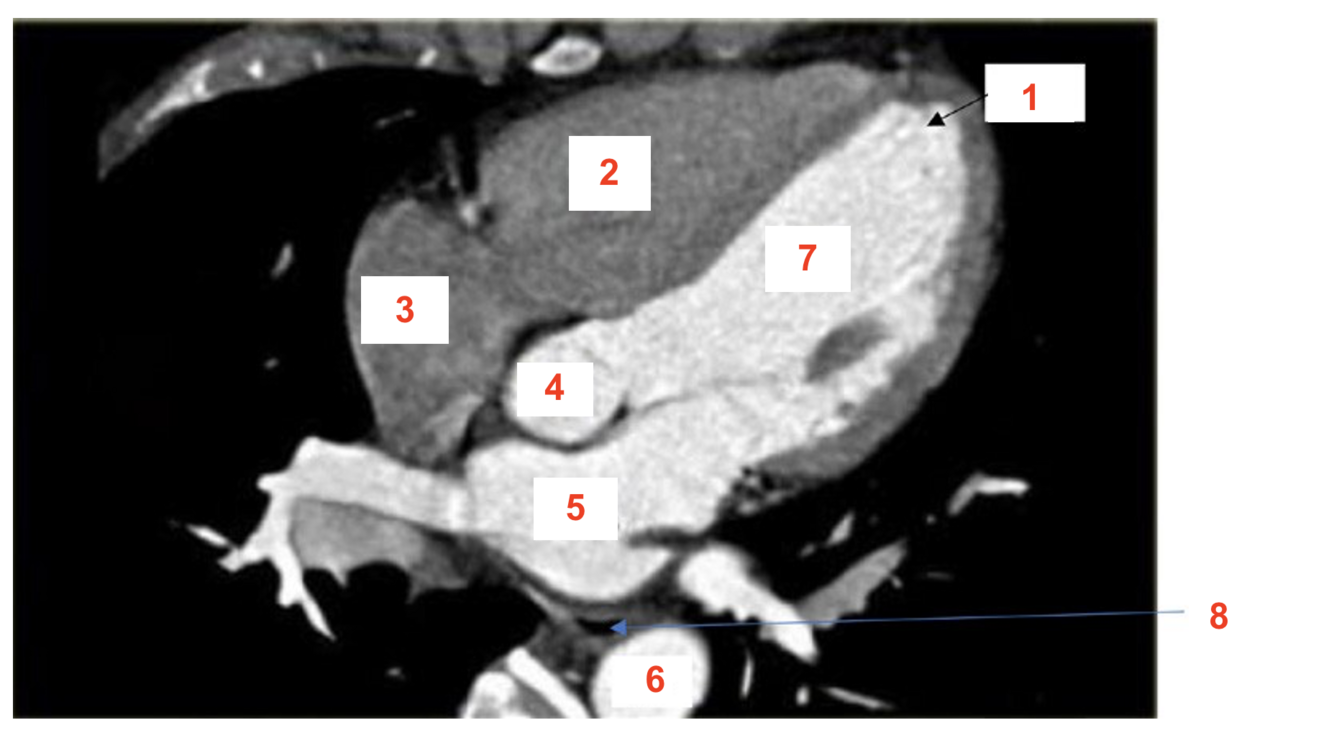

label 1

RV

2

Apex

3

RA

4

LV

5

oesophagus

6

LA

7

aorta

8

azygos vein